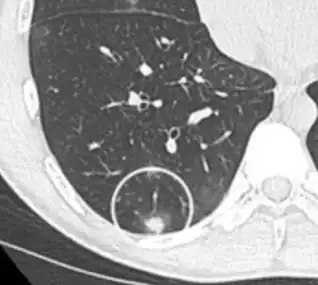

Thin slice and maximal intensity projection of a lung nodule, the latter better visualizing vascular convergence.[9]

• Vascular convergence is where vessels converge to a nodule without adjoining or contacting the edge of the nodule, and is mainly seen in peripheral subsolid lung cancers.[9] It reflects angiogenesis.[9]